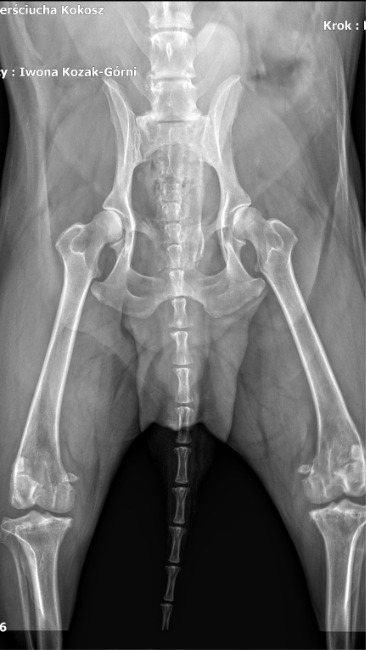

To tak dzielny, wspaniały, kochany zwierzak, że ciężko uwierzyć, że kilka dni temu przeszedł taką ciężką operację.

Nóżka Kokoszka, choć nadal obrzęknięta, dobrze się goi i nasz dzielny psiak stawia na niej swoje wielkie łapeczki.

Sam Kokosz jest teraz taki uśmiechnięty i pogodny, że wiemy, że decyzja o wykonaniu u niego pierwszej z trzech operacji łapek była słuszna i najlepsza.

Fot. Droga chłopaków do równowagi psychicznej. Wizyty w gabinecie lek.wet.